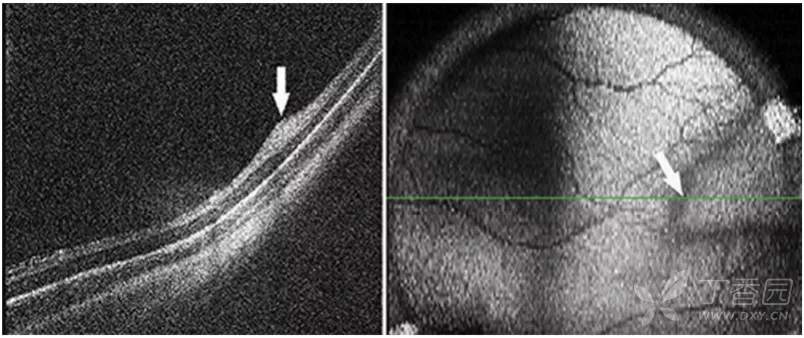

急性ROP4期OCT图像

图. 4A期视网膜脱离:OCT可见中心凹视网膜附着(星号),视网膜内渗出(高反射点)、周边部视网膜脱离和视网膜劈裂。

图. 4B期视网膜脱离:OCT可见中心凹视网膜脱离(星号),在检眼镜检查中很难识别。